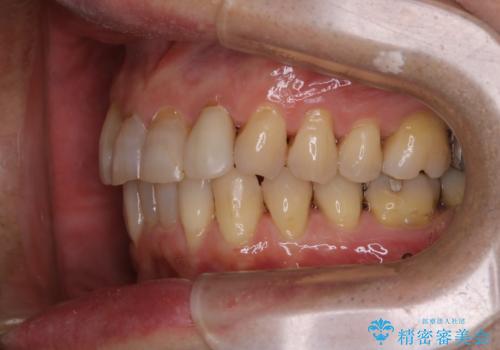

- インビザラインでの矯正中も、コーヒーを頻繁に飲むためステインが気になるとのことでした。PMTC60分コースでなんとかクリーニングを行いました。

インビザライン治療中には、歯の表面にアタッチメント(効率的に歯の移動をするもの)を設定します。そのため歯ブラシでは届きにくい細かい部分などに、歯石や着色がついてしまうことがあります。着色などを放置していると、着色なのか、虫歯なのかの判別もしずらく正確にお口の中の状態を診断できません。

矯正治療中も定期的に歯科医院にてPMTCを受けて、お口のケアを行うことをおすすめします。